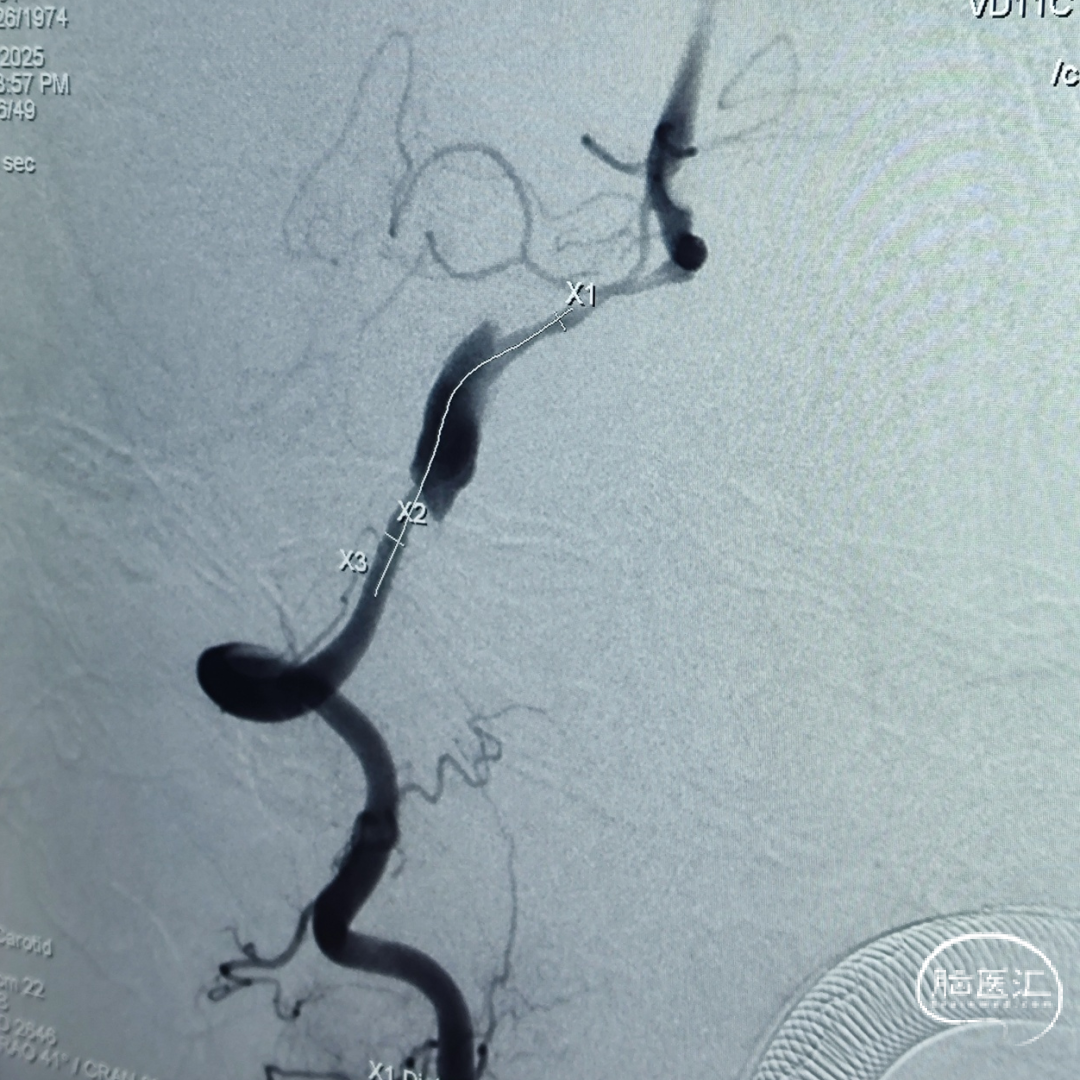

盖延廷教授病例分享一:左侧颈内动脉多发动脉瘤

患者:女性,55岁。

主诉:头疼,检查发现动脉瘤8月余。

入院查体:颅内多发动脉瘤。

术前诊断:

左侧颈内动脉:

右侧颈内动脉:

远端锚定点脉前起始近端;近端锚定点海绵窦段。

载瘤动脉远端血管直径:3.23 mm

载瘤动脉近端血管直径:4.17 mm

选用4.25mm*25mm 强易达(Choydar)密网支架。

术后即刻造影。

术后重建。